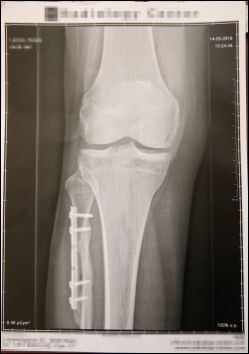

Renate L. (70) brach sich im Dezember 2017 den rechten Unterschenkel. Ein Unfall-Chirurg setzte ihr eine Titan-Platte ein. Diese schädigte einen Nerv schwer.

"Mein Unterschenkel ist komplett taub. Vor kurzem ist mir ein Suppentopf aufs Bein gefallen, und ich hab gar nix gespürt", erzählt Renate L. (70). Die Pensionistin aus Purkersdorf bei Wien gibt der Titan-Platte die Schuld, die ihr auf Anraten eines renommierten Unfall-Chirurgen eines Wiener Privatspitals im Dezember 2017 eingesetzt wurde: "Ich hatte monatelang Schmerzen, und habe immer wieder darauf hingewiesen. Er hat nur gemeint, es ist alles in Ordnung", meint Renate L.

Schließlich wurde im heurigen März ein Röntgen gemacht: "Daraufhin meinte der Chirurg: 'Die Platte muss raus'", so die 70-Jährige. Inzwischen hatte die Titan-Platte einen Nerv derart gereizt, dass dieser schwer geschädigt ist: "Ich mache Physiotherapie, gehe massieren und muss eine Schiene tragen. Aber es ist nicht besser geworden. Im Gegenteil: Ich habe oft das Gefühl, ein Messer sticht in mich rein."